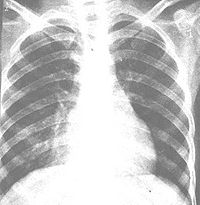

腺病毒性肺炎透视

2.X线检查

X线形态与病情、病期有密切关系。肺纹理增厚、模糊为腺病毒肺炎的早期表现。肺部实变多在发病第3~5天开始出现,可有大小不等的片状病灶或融合性病灶,以两肺下野及右上肺多见。发病后6~11天,其病灶密度随病情发展而增高,病变也增多,分布较广,互相融合。与大叶肺炎不同之处是,本病的病变不局限于某个肺叶。病变吸收大多数在第8~14天以后。有时若病变继续增多、病情增重,应疑有混合感染。肺气肿颇为多见,早期及极期无明显差异,为双侧弥漫性肺气肿或病灶周围性肺气肿。1/6病例可有胸膜改变,多在极期出现胸膜反应,或有积液